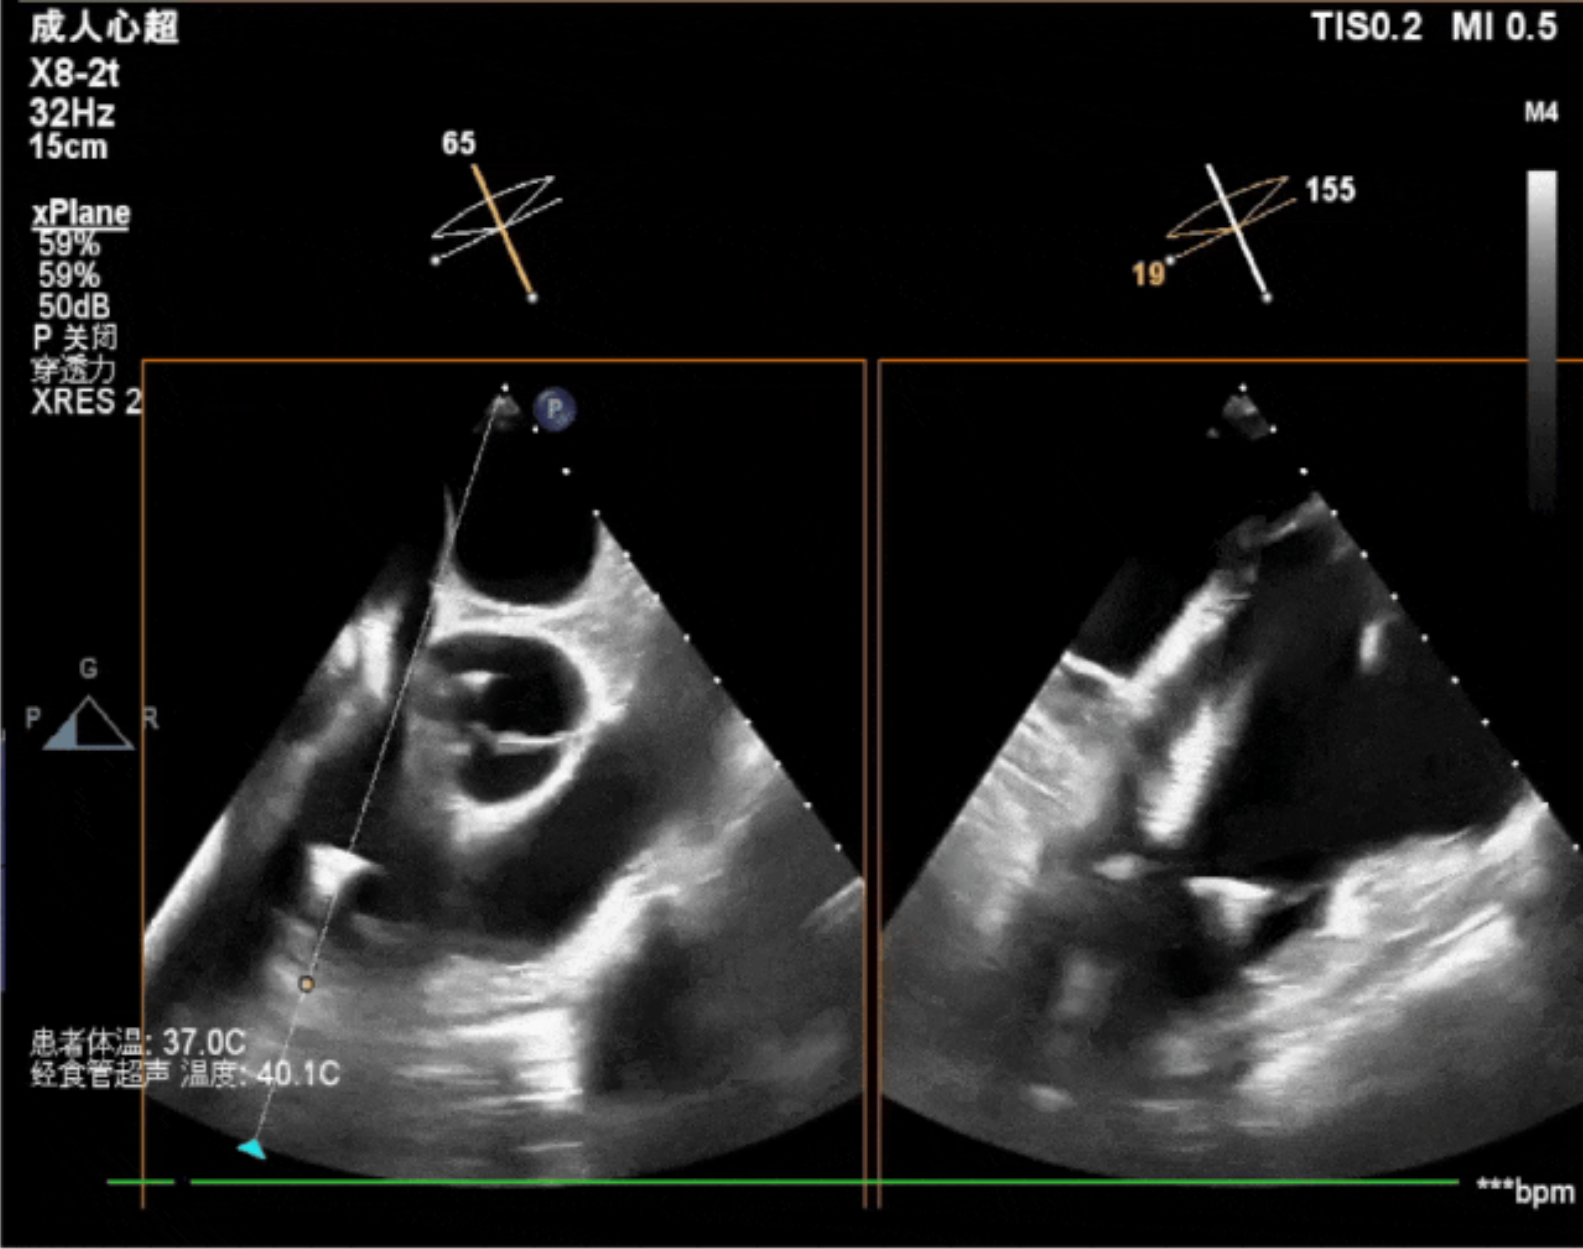

術中經食道超聲輔助下可見LuX-Valve Plus夾持件抓捕瓣葉狀態良好,夾持件在位,室間隔錨定位置良好,假體瓣膜整體錨定狀態穩固。

術后即刻經食道超聲可見,三尖瓣假體瓣膜位置合適,牛心包瓣葉運動狀態良好,開閉正常,瓣周及瓣葉對合緣處未見明顯返流,心電圖及心包狀態較術前無明顯變化。

今天我們見證了一臺嫻熟、優雅且迅速的經導管三尖瓣置換手術,我們可以看到的是,手術完成后的三尖瓣超聲指標非常完美,值得一提的是,經食道超聲技術在整臺手術中有著非常重要的作用,我們可以用幾個簡單的切面精準的指引LuX-Valve Plus的植入,相信在未來,超聲在三尖瓣介入置換圍術期中將有著更重要且成熟的應用。